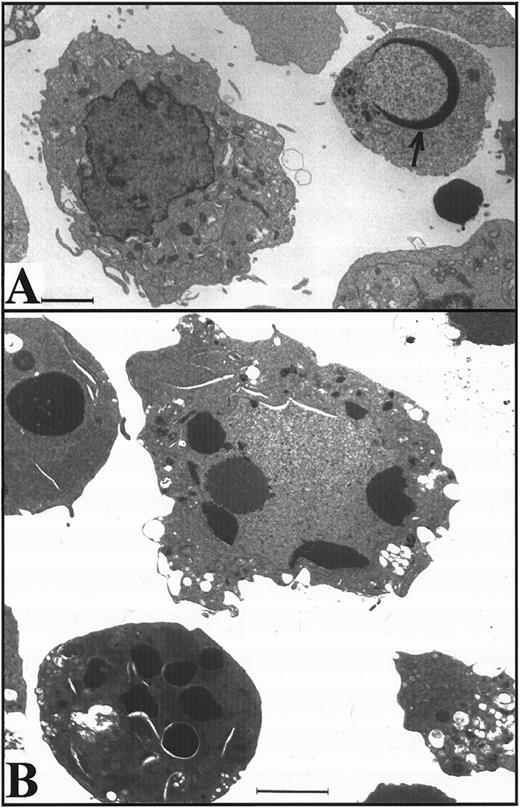

K562 cells treated with 17 μmol/L etoposide for 1 hour undergo delayed apoptosis. (A and B) Electron micrographs of K562 cells before (A) and 48 hours after (B) a 1-hour treatment with 17 μmol/L etoposide. Bar, 2 μm. (C and D) Samples of HL-60 cells (lanes 1, 2) and K562 cells (lanes 3 through 8) were treated with 17 μmol/L etoposide for 0 hours (lanes 1 and 3) or 1 hour (lanes 2 and 4 through 8) and incubated in drug-free medium thereafter. At the indicated times, samples were obtained and subjected to SDS-PAGE followed by immunoblotting with monoclonal anti-PARP (C) or agarose gel electrophoresis (D). (E) Total cell number of K562 cells following a 1-hour exposure to 17 μmol/L etoposide and cell-cycle distribution of the resulting nonapoptotic cells. (Inset) DNA histograms obtained before and 1 day after a 1-hour exposure of K562 cells to 17 μmol/L etoposide. (F) Percentage of K562 cells that exhibit apoptotic morphology and trypan blue uptake after a 1-hour exposure to 17 μmol/L etoposide. (Inset) Photograph of K562 cells stained with 1 μg/mL Hoechst 33342 at the indicated time after a 1-hour etoposide treatment. Arrows, cells with chromatin condensation and nuclear fragmentation indicative of apoptosis. Each panel is representative of at least three experiments.

Apoptosis is delayed in K562 cells even after treatment with higher doses of etoposide.The long latent phase and lack of synchrony after treatment of K562 cells with 17 μmol/L etoposide made it difficult to perform additional biochemical studies under these conditions. Previous studies have indicated that increasing the etoposide concentration to 68 μmol/L, a concentration that is readily achievable in the bone marrow transplant setting,61,62 results in more synchronous induction of apoptosis in HL-60 cells, with greater than 85% of cells exhibiting apoptotic morphology within 6 hours.32 When this same strategy was applied to K562 cells, a population of cells with condensed peripheral chromatin was visible at 24 hours (arrow, Fig 3A). At 48 hours, 80% of cells displayed increased electron density (indicating loss of H2O) and peripheral chromatin condensation or nuclear fragmentation when examined by light (not shown) or electron microscopy (Fig 3B). Oligonucleosomal DNA degradation (Fig 3C) as well as proteolytic cleavage of PARP and lamin B1 (the latter detected as loss of intact 67-kD polypeptide in Fig 3D) were readily evident 48 hours after addition of etoposide. Collectively, these observations again indicated that K562 cells demonstrate typical apoptotic changes, although their development was markedly delayed relative to HL-60 cells.

Apoptosis in K562 cells treated continuously with 68 μmol/L etoposide. (A and B) Morphology of K562 cells after 24 hours (A) and 48 hours (B) continuous exposure to etoposide. Arrow in (A), peripheral chromatin condensation in K562 cell after 24-hour etoposide exposure. Bar, 2 μm. (C and D) HL-60 cells treated with etoposide for 0 to 6 hours (lanes 1 through 6) and K562 cells treated with etoposide for 0 to 48 hours (lanes 7 through 10) were harvested for agarose gel electrophoresis (C) and SDS-PAGE followed by blotting with C-2-10 anti-PARP or polyclonal anti-lamin B1 antibodies (D). Arrow indicates 89-kD cleavage product of PARP.